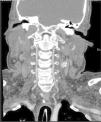

La angiografía computarizada constató en todos los casos la detención del contraste al nivel del agujero magno sin visualizarse contraste en arterias vertebrales intracraneales. Al estudiar la circulación anterior se visualiza un afilamiento progresivo de las arterias carótidas internas en el cuello, comprobándose que el contraste se detiene en la porción petrosa carotídea, y demostrándose la ausencia de relleno de las arterias carótidas internas intracraneales. Se observa relleno de contraste en las diferentes ramas de las arterias carótidas externas (figs. 1-4).

Figura 1. Angio-tomografía computarizada que demuestra la ausencia de circulación intracraneal. Las flechas finas indican las ramas arteriales de la arteria carótida externa y la flecha gruesa la craneotomía.